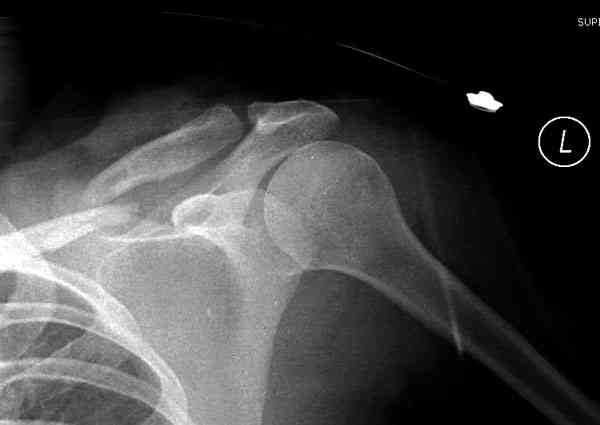

iГГШ> выполнения новокаиновой блокады дежурной бригадой выполнена закрытая

ГГШ> репозиция, наложены кольца Дельбе. Результаты репозиции показаны на

ГГШ> Результат стационарного лечения приведен на рентгенограмме (Xray_3).

Это картинка то есть через неделю после травмы, при выписке? Более чем приемлемо.

Травма амбулаторная, смещение изначально было допустимым, но можно было и подправить, только мы у старших детей применяем шинно-гипсовую повязку. В данном случае репозиция положения не улучшила, на последних рентгенограммах положение отломков удовлетворительное. С уважением, А.В. Шахин

1) после репозиции стало хуже

2) стояние фрагментов при выписке идентично таковому при пступлении - с выраженным смещением

Распределение мнений по перечисленным выше категориям приведено на гистограмме (см. Рисунок 1). Мнения разделись, и в аудитории преобладает убеждение, что сохранение смещения ключи.цы на величину диаметра без кортикального контакта между отломками и смещением до 3 см по длине у подростка 15 лет допустимо.